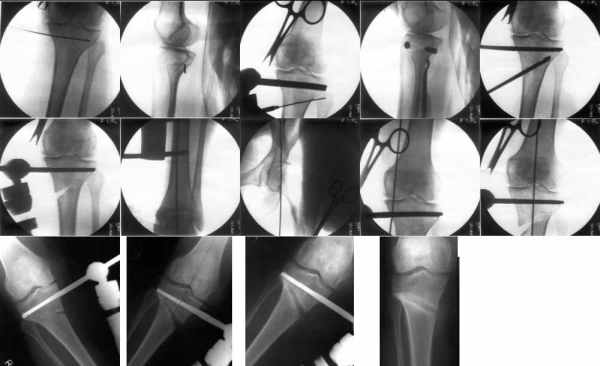

I do upper tibial osteotomies with either an ilizarov fixator and acute correction of the deformity or with an orthofix with gradual correction.

Sending you pics of the steps of the osteotomy and the frame.

You can do the osteotomy in a "focal dome" or in a transverse fashion. The dome has the advantage of having a good contact, allowing weight bearing as tolerated early on.

The level is below the tibial tuberosity.

The frame I use is pretty simple, with one wire each in the proximal and distal ring, two schanz pins in the proximal ring, and one each in the middle and distal ring.

I preconstruct a frame with the proximal ring in varus by the use of coupled washers in the threaded rods in the front and back. These are used as hinges, and after the correction, a medial and lateral threaded rod is also added.

Since the center of rotation of these deformities is usually near the knee joint line, lateral translation of the distal fragment is necessary to normalise all the axes.

You can also do the osteotomy in a transverse fashion.

When I use an orthofix fixator, the osteotomy is oblique, starting below the tuberosity and ending 1 cm away from the lateral cortex at the level of the head of the fibula. No fibular osteotomy is needed there. The deformity is gradually corrected over 2 or three weeks.

You could also do the same with an ilizarov fixator